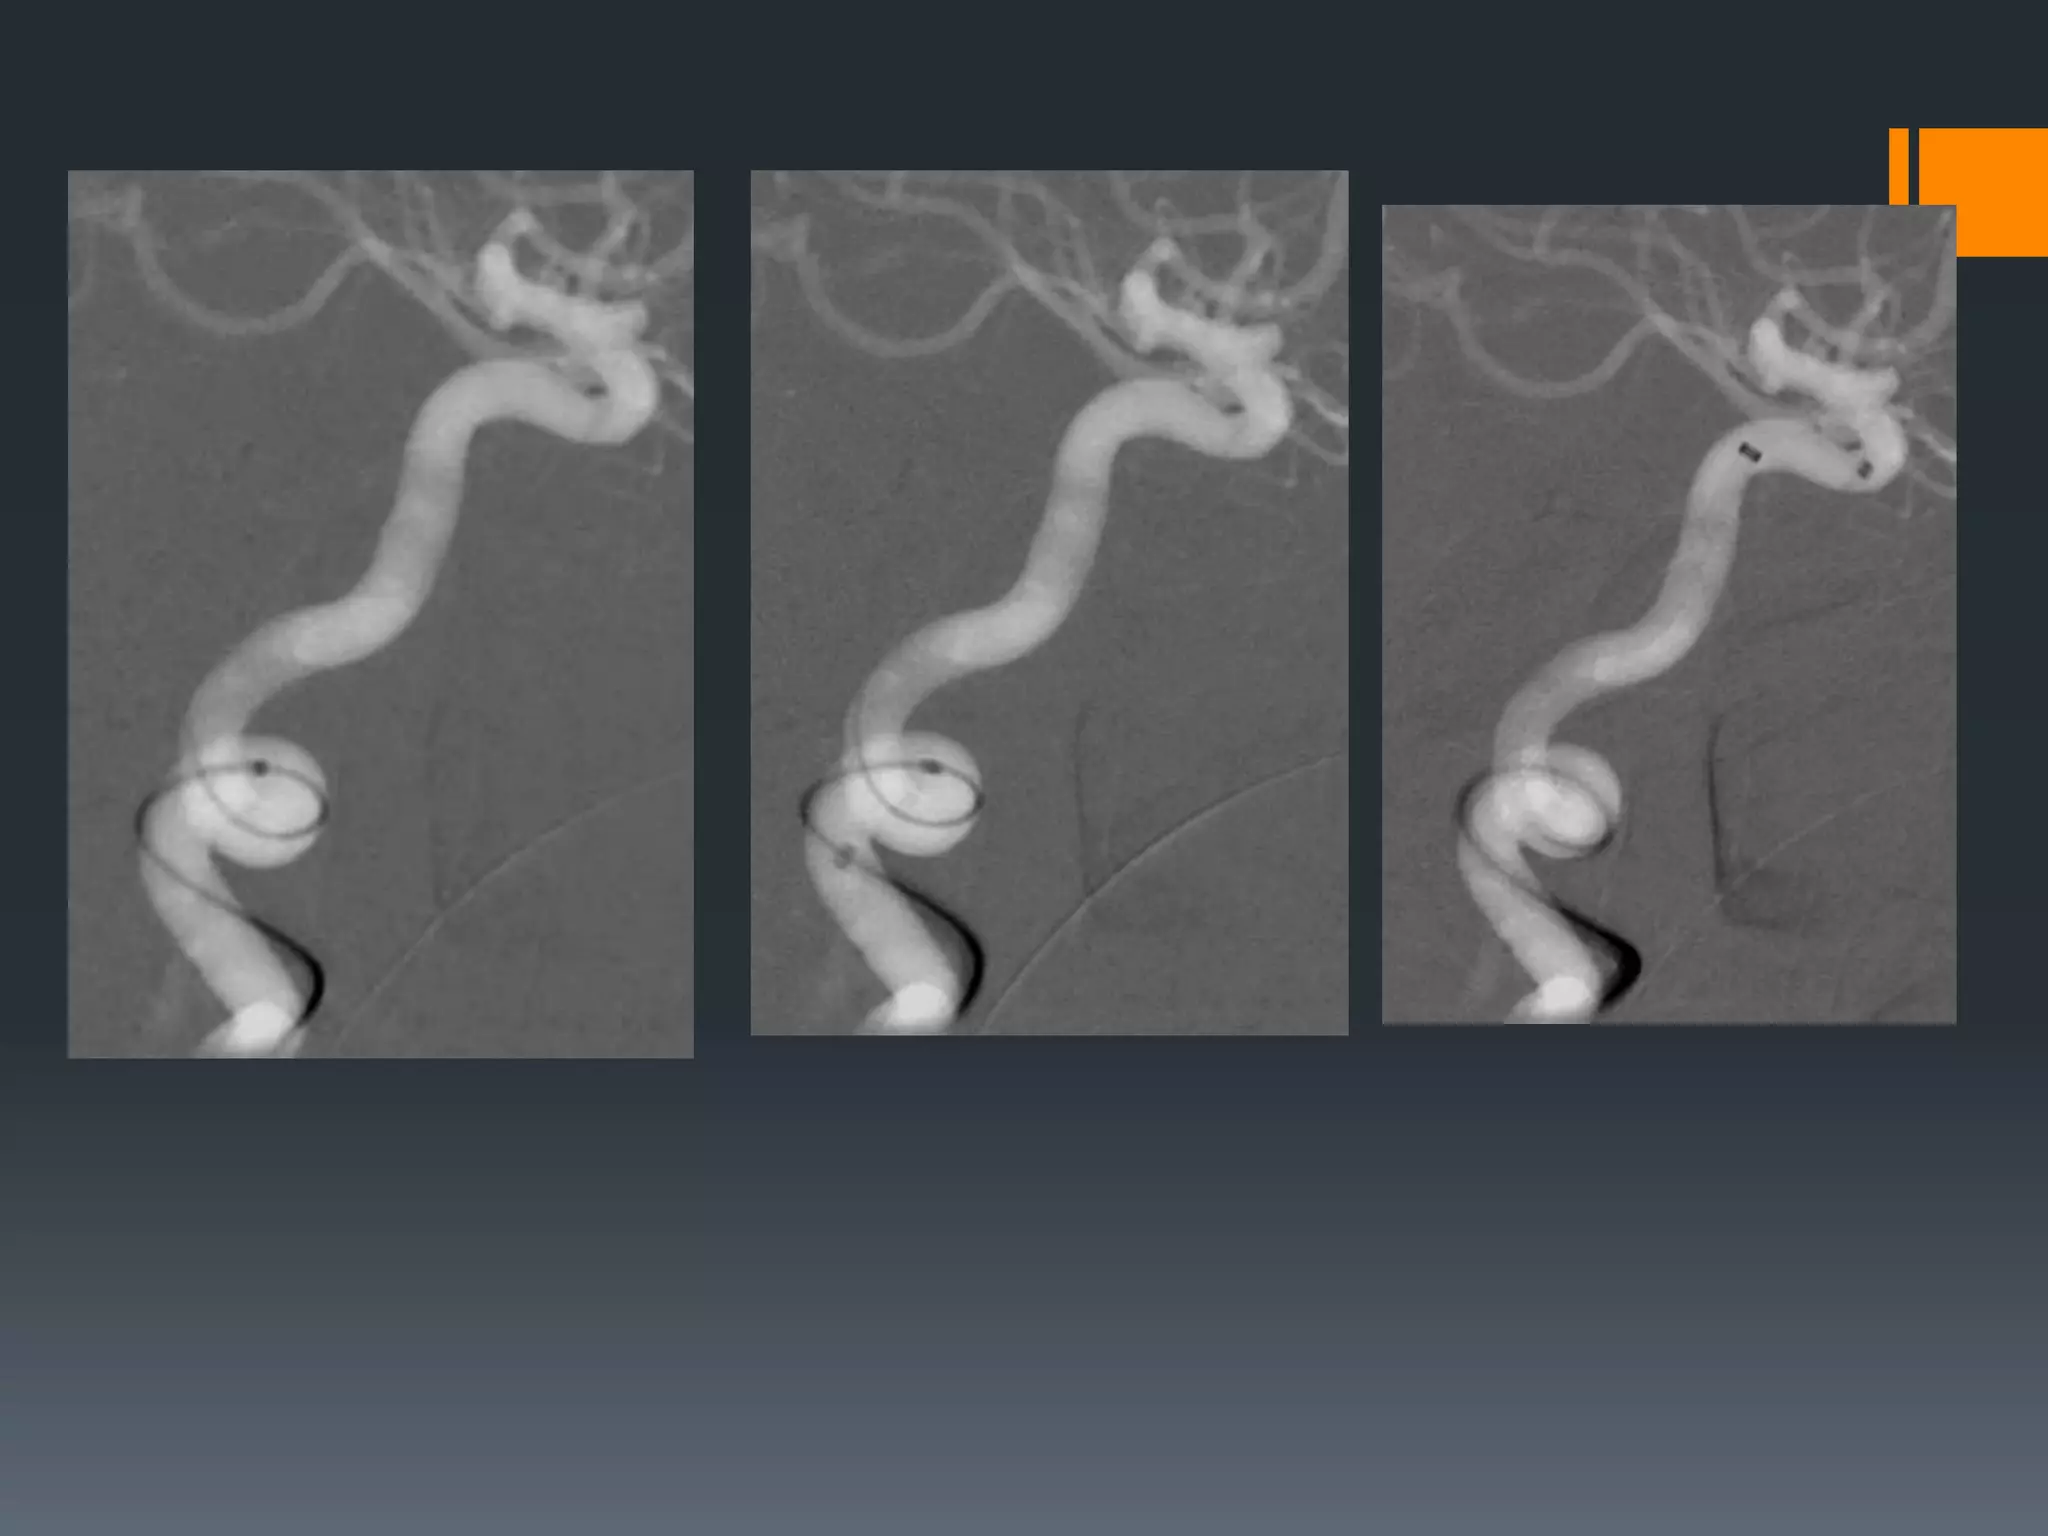

This document discusses tricks and techniques for difficult cannulations during neurointerventional procedures. It outlines strategies for accessing the aortic arch, internal carotid artery (ICA), and areas distal to aneurysms. Long sheaths, distal access catheters, and co-axial techniques are presented as options that have improved cannulation success. Guidance on sheath and catheter selection is provided for different vessel paths. The importance of catheter placement as high as possible in the ICA is emphasized. Reverse curve cannulations are also mentioned. Overall, the document stresses that careful cannulation is critical for procedural success and different strategies may be needed depending on the vessel target.